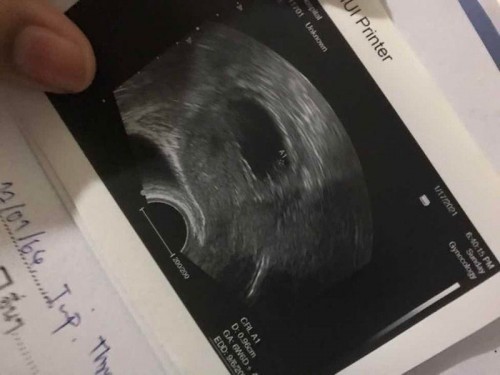

เมื่อวานไปหาหมอมาค่ะ แต่หมอไม่ได้ฉีดยากันแท้งให้จะเป็นอะไรไหมคะ ตอนนี้ได้12weekแล้วค่ะ หมอซาวดูบอกยังไม่ได้ยินเสียงหัวใจ แต่เห็นน้องเป็นตัวเล็กมากๆ หมอบอกว่าให้รอดูไปอีกสักพักไม่ทราบว่าจะปกติไหมคะ (หมอบอกให้นอนเฉยๆอยู่บ้านเดินให้น้อยที่สุด เราสามารถนั่งได้ไหมคะ)#ท้องแรกคะ #ขอบคุณล่วงหน้านะคะ #ขอคำแนะนำค่ะ

ของเราตรวจเจอน้องตอน 7w หัวใจยังไม่เต้น เจอภาวะแท้งคุกคามเหมือนกันค่ะ มีเลือดออกรอบๆถุงตั้งครรภ์ หมอนัดอีกทีตอน 12w เริ่มมีหัวใจเต้น หมอแนะนำให้อยู่เฉยๆ ห้ามยกของหนัก เดินได้ แต่อย่าเดินบ่อย ลองทำตามที่หมอบอกนะคะ ตอนนี้31w แล้วน้องแข็งแรงสมบูรณ์ดีค่ะ